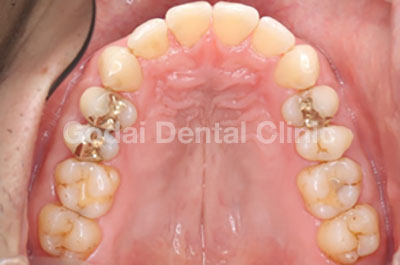

治療前

患者様は30代男性、上の歯が一本前に出ていることと、下の歯がガタガタになってきたのが気になるという理由で来院されました。奥歯の噛み合わせに機能的な問題はなかったため、主訴である前歯の治療のみを行うことになりました。歯並びを治すには様々な矯正方法がありますが、患者様と相談した上で今回はマウスピースを用いた矯正を行うことになりました。 マウスピース矯正には以下のメリットがあります。

実際の治療ですが、週に1回のペースでマウスピースを交換していただき、上の前歯が出ていることと・下の前歯がガタガタになっていることの2点をたった3ヶ月で改善することができました。患者様も「全く目立たないので同僚にも矯正をしていると気付かれなかった。痛みもほとんどなかった。いつでも取り外すことができるため、食事や歯磨きにも普段と同じように行うことができた。治療期間も短いので最後までやり通すことができた。何より前歯がキレイに並んだのがとても嬉しかった。」と、喜びのコメントをいただきました。全顎的な矯正をやることには抵抗があるが、前歯のガタガタや空隙を治したいと考えている方は、ぜひ一度相談にいらしてください。

| 治療内容 | 矯正治療(インビザラインGO) |

| 概算治療費 | 約40万円 |

| 治療期間 | 約4ヶ月 |